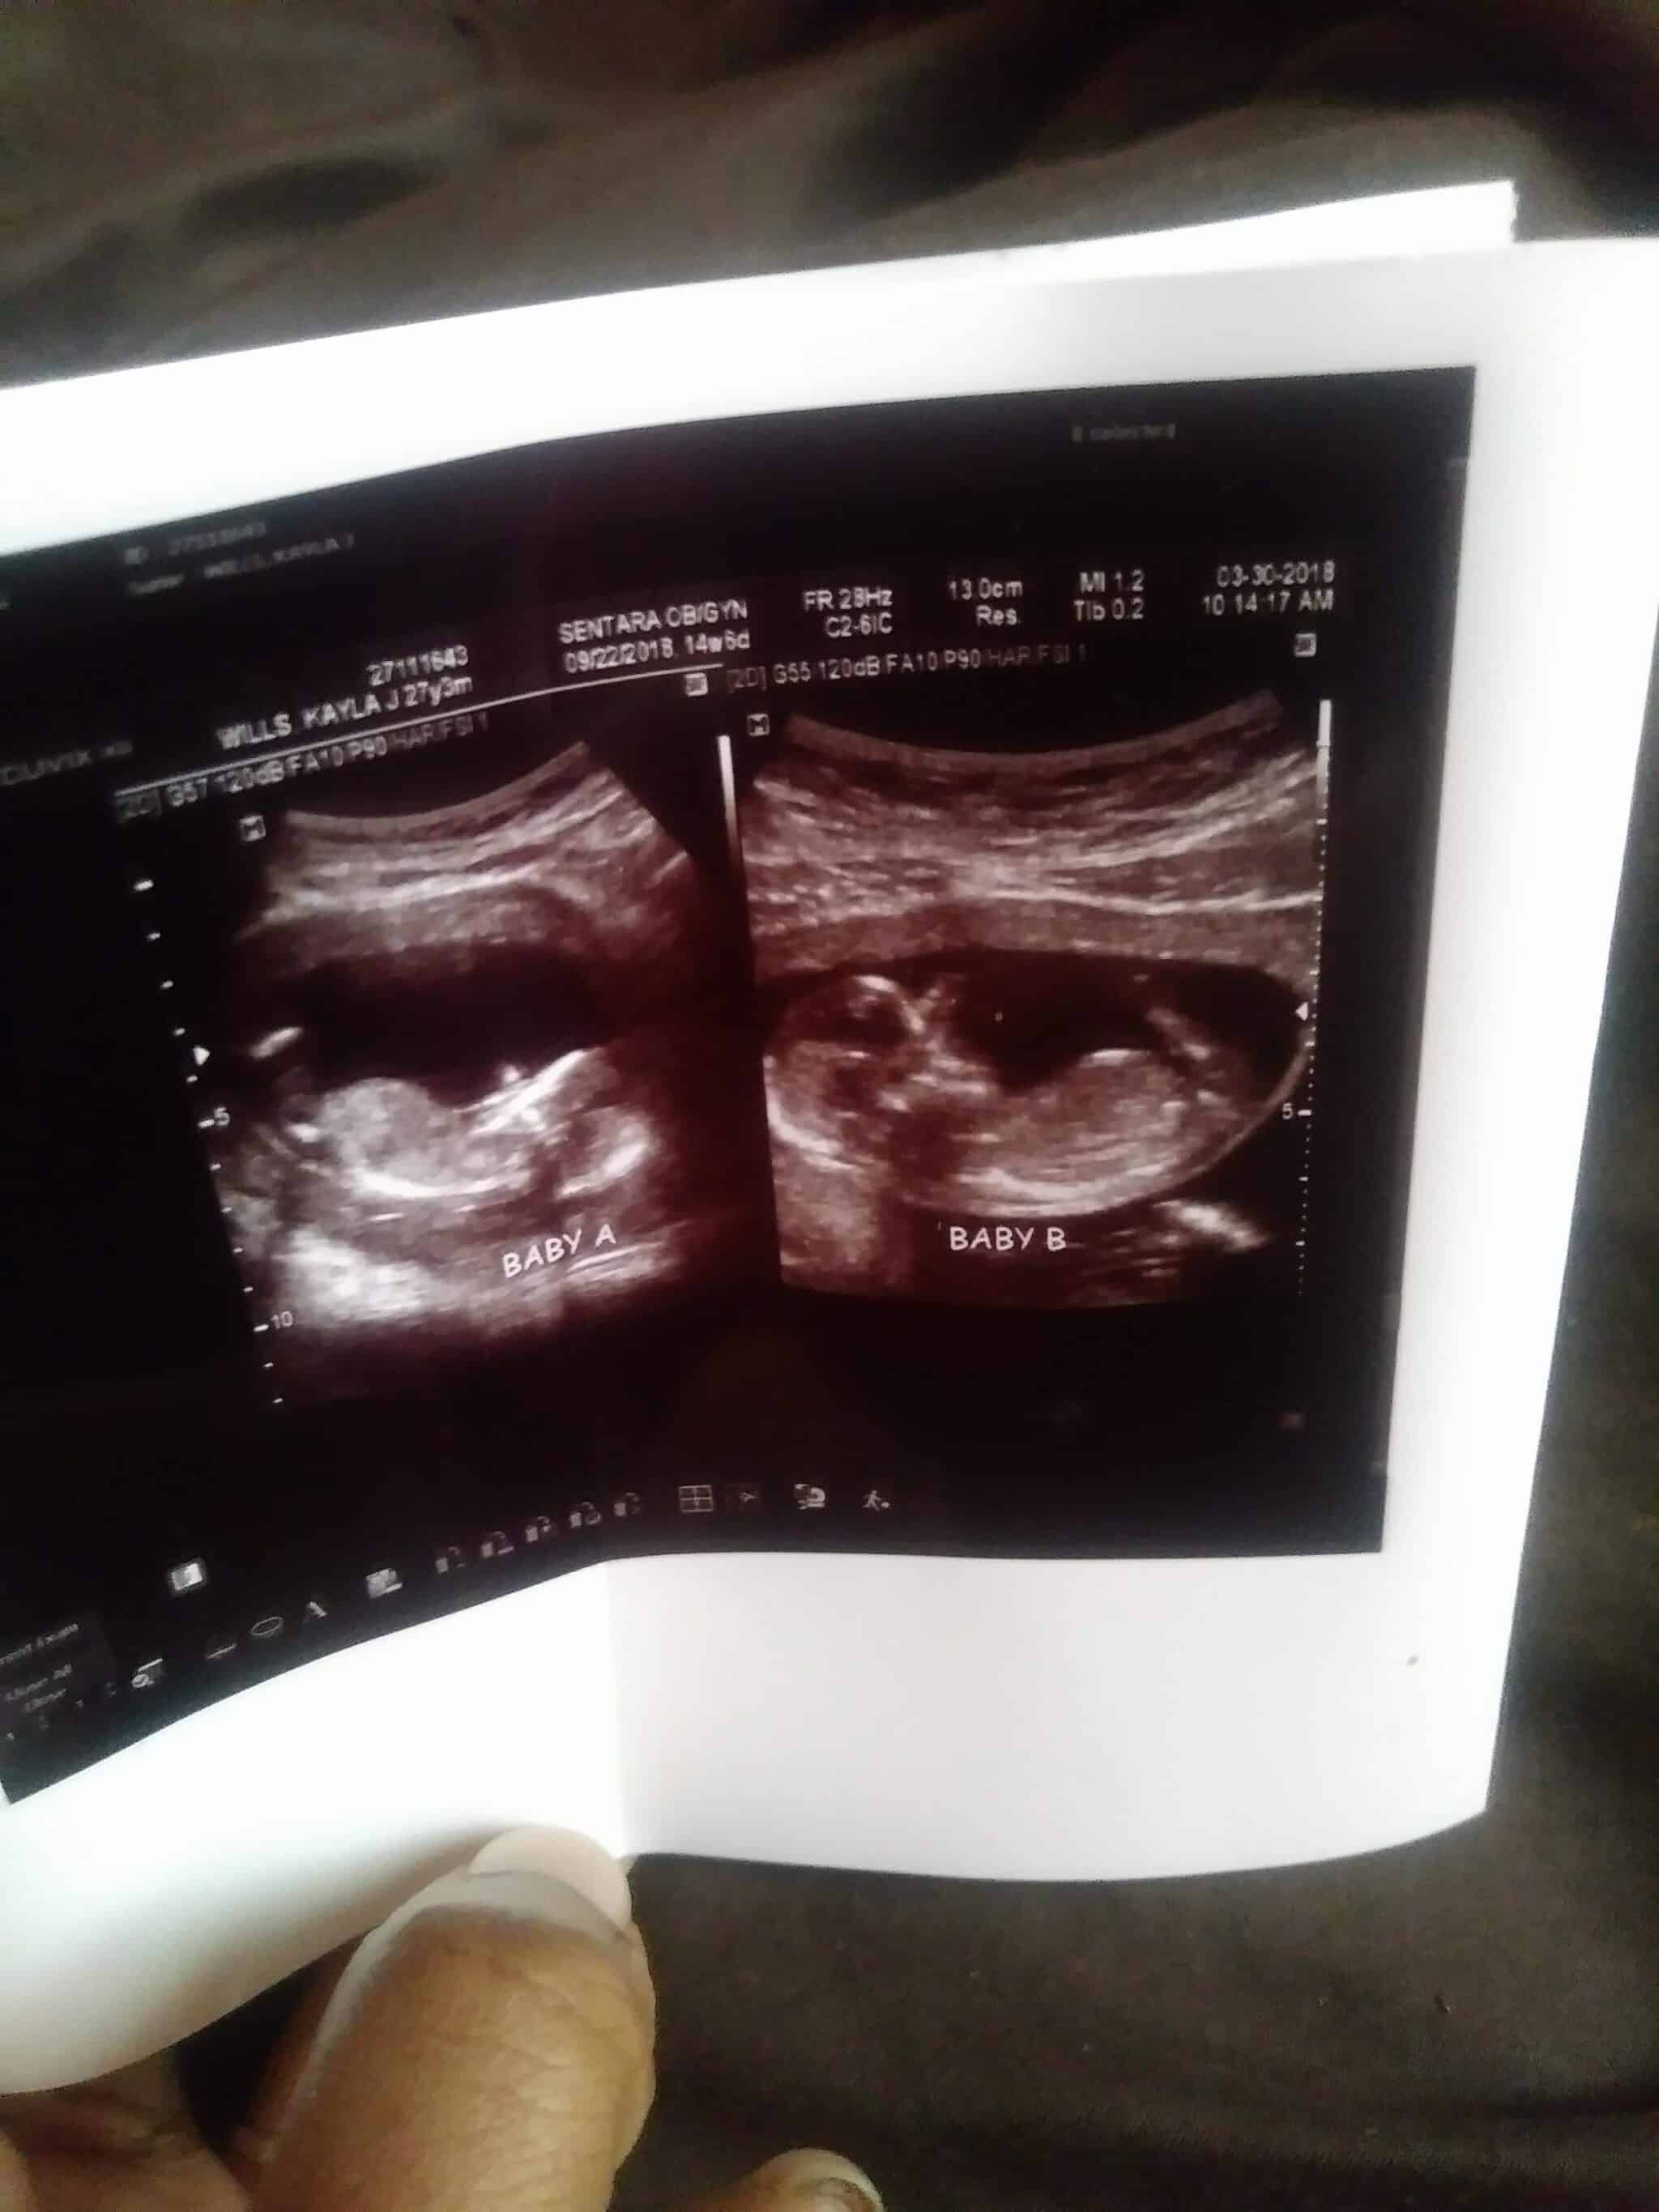

Ultrasound Photos at 27 Weeks Pregnant With Twins